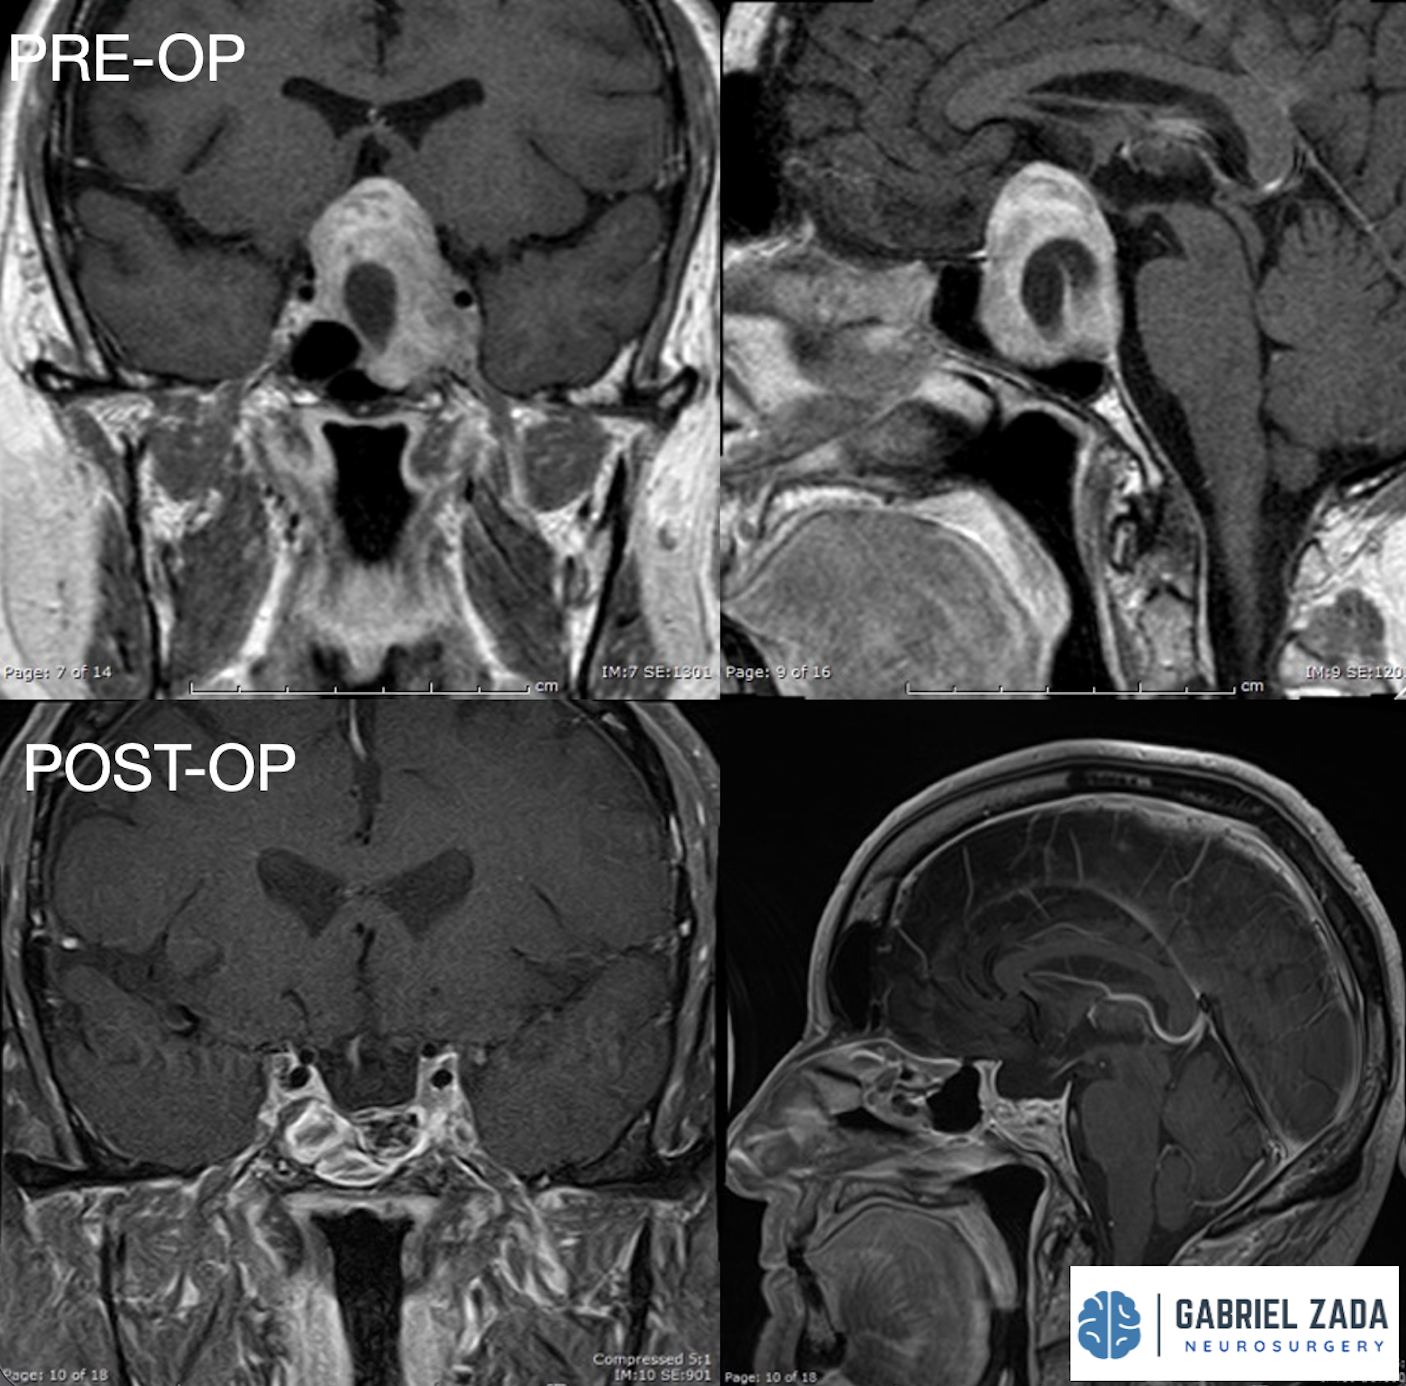

Craniopharyngioma treatment

• Complex tumors near the pituitary gland that require specialized neurosurgical expertise.